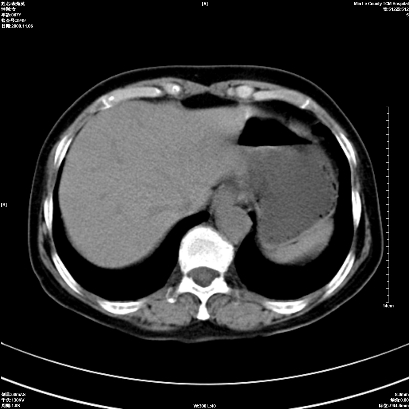

以下是引用卜一在2008-11-6 15:58:00的发言:[br]胰头略增大,胆总管扩张,末端渐行性狭窄。多考虑:胰头癌!建议增强!